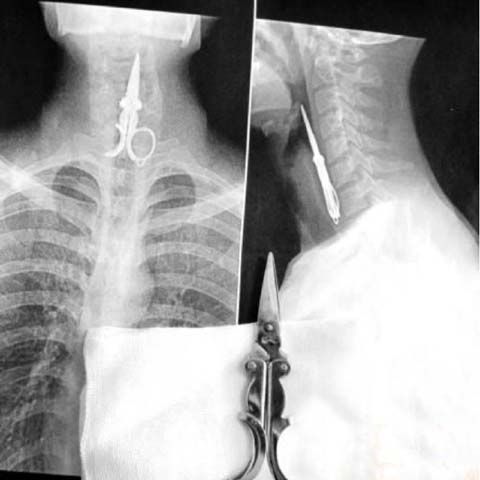

1 apr. 2009, 14:29Ultimele StiriUn chinez a ajuns la spital cu o forfecuţă de unghii înfiptă în esofag